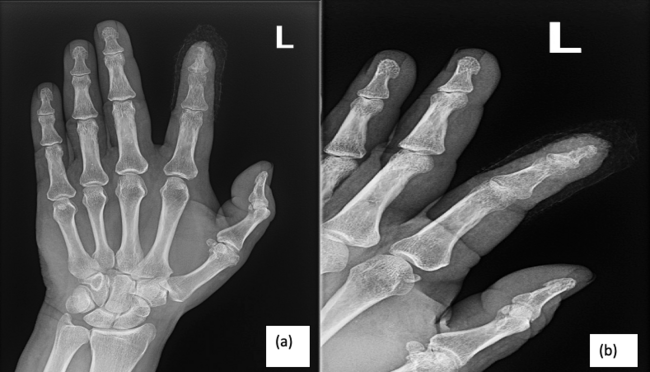

The patient described a crush injury to the same digit 2 years prior to presentation due to a cinder block falling onto his finger. He had since been experiencing persistent pain, which intensified over time. Radiographic images taken at a health facility affiliated with the Department of Corrections from a few months prior to presentation confirmed the presence of osteomyelitis compromising the middle and distal phalanges as well as the distal interphalangeal joint of the left index finger (Figure 1). However, no interventions were pursued at the time due to complications related to the patient being subject to permanent house arrest with inconsistent transportation to and from appointments, as well as the restraints imposed by the COVID-19 pandemic.

Figure 1. Radiographic images obtained prior to surgery demonstrating lucency and cortical erosion of the distal phalanx and distal portion of the middle phalanx of the left index finger consistent with osteomyelitis. (A) posteroanterior view, (B) lateral view.